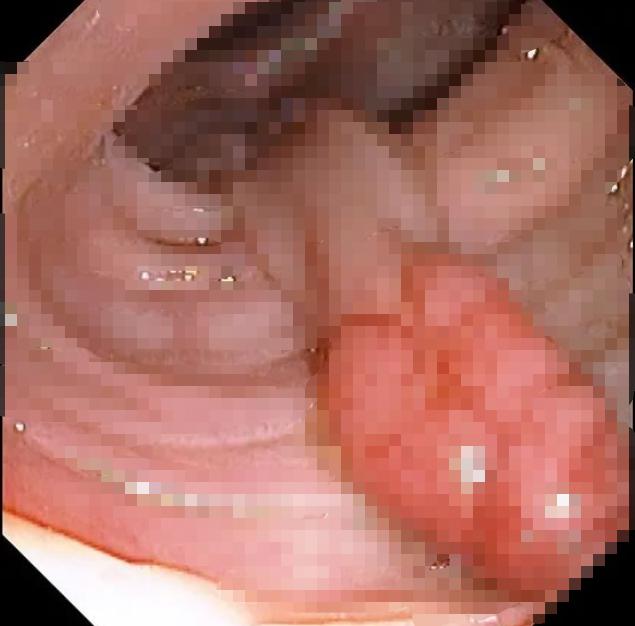

患者章阿姨(化名),41岁,体检时检查粪便隐血阳性,医生建议进行肠镜检查,肠镜提示:结肠息肉(升结肠:近肝曲可见一1.3cm丘样隆起,表面光滑),但张女士无明显不适。

息肉是肠道内表面粘膜多出来的赘生物,就像个“肉疙瘩”。主要见于大肠(结肠和直肠),而小肠(十二指肠、空肠和回肠)比较少见。大肠息肉可以是单个发生,也可以是几个、几十个或者更多发生,多数有蒂,少数是广基的。